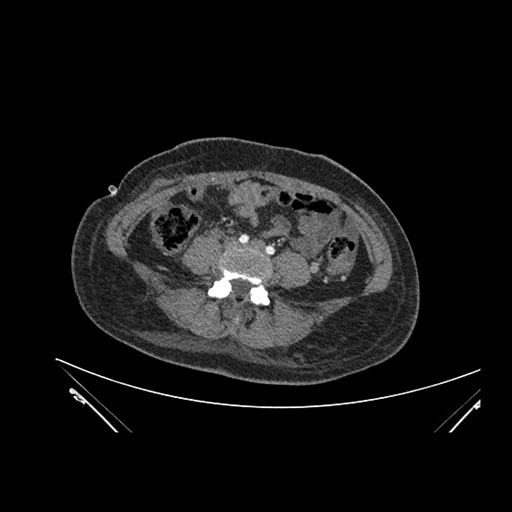

Imaging Analysis

Look through the patient's CT scan to identify any areas of concern for the necessary procedure.

Based on initial findings, which issue(s) would you be most concerned about?